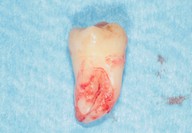

Galleria fotografica